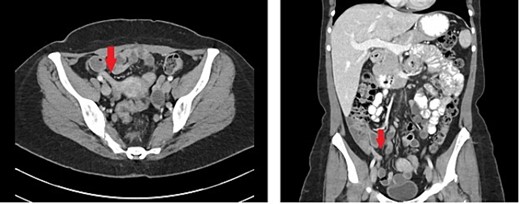

A 42-year-old female with a past medical history significant for gluten intolerance and seasonal allergies presented to the emergency department with a three-day history of right lower quadrant abdominal pain and poor appetite in conjunction with reported fevers at home as high as 38.6°C. The pain was progressively worsening and associated with non-bloody, non-bilious emesis on three occasions. On examination, there was tenderness in the right lower quadrant, with localized guarding and rebound tenderness at McBurney’s point. Laboratory investigations revealed a normal white blood cell count (4900/μl) without a left shift or eosinophilia. A computed tomography (CT) scan (Fig. 1), showed an 8 mm dilated appendix with peri-appendiceal fat stranding, suggestive of acute appendicitis.

Representative axial and coronal cuts of CT imaging showing an 8 mm dilated appendix noted by the arrow.